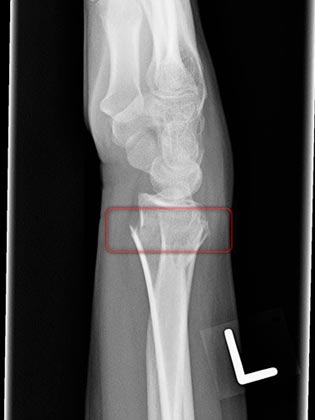

The mountain we’re climbing is in Kananaskis. We booked the trip to celebrate my 25th birthday [that happened over 2 months ago]. It’s been a long time coming, but the day is finally upon us. Honestly though, I have no idea why I chose this activity to ring in my 25th. Maybe to prove to myself that I can accomplish anything I put my mind to? Have I mentioned that I’m afraid of heights? It should also be said that I have a history of breaking limbs in the mountains. Case in point, 1.5 years ago when I was snowboarding on vacation… After this experience, I’m probably one of the only Canadians that is afraid of the mountains, snow, and anything to do with strapping myself to a piece of fiberglass and going headfirst down a mountain. I’ll stick to water skiing, thank you very much :P I keep asking Kevin to promise me that I wont break anything, but he just giggles and smiles. It’ll be fine, I’m sure of it. And if not, at least I’ll have a big healthy lunch with me!